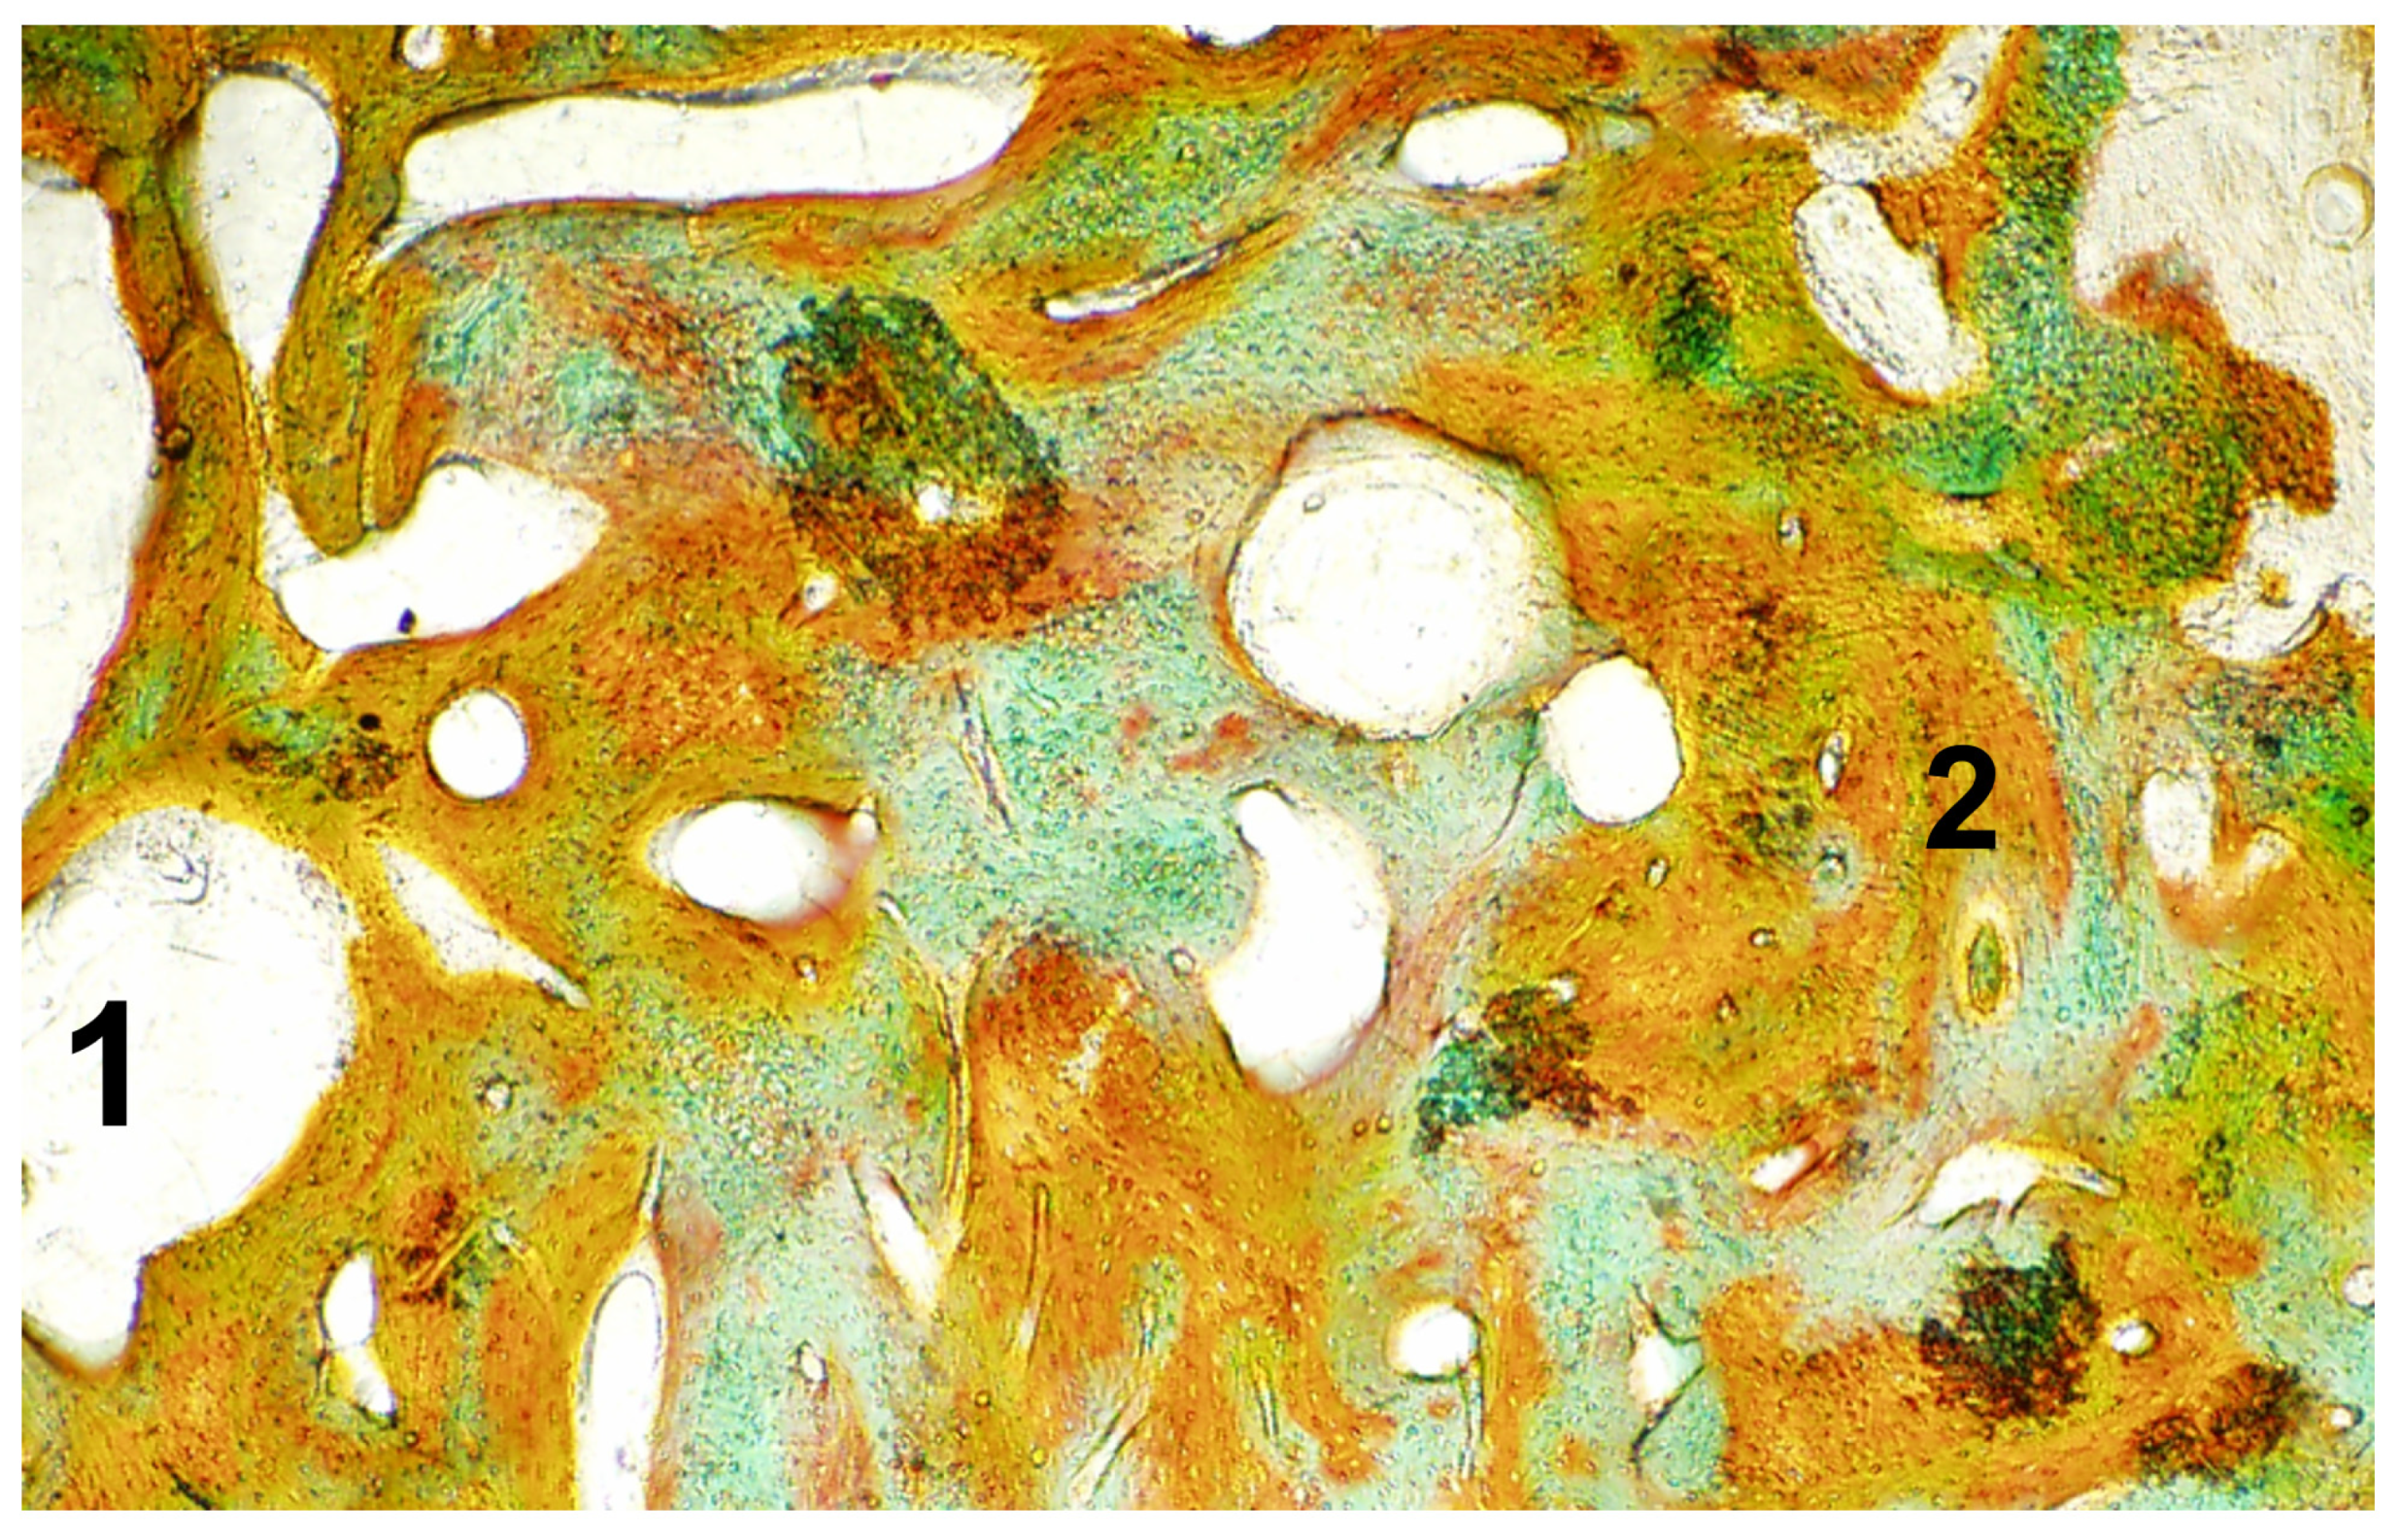

Macroscopic, Microscopic, and Radiological Evaluation